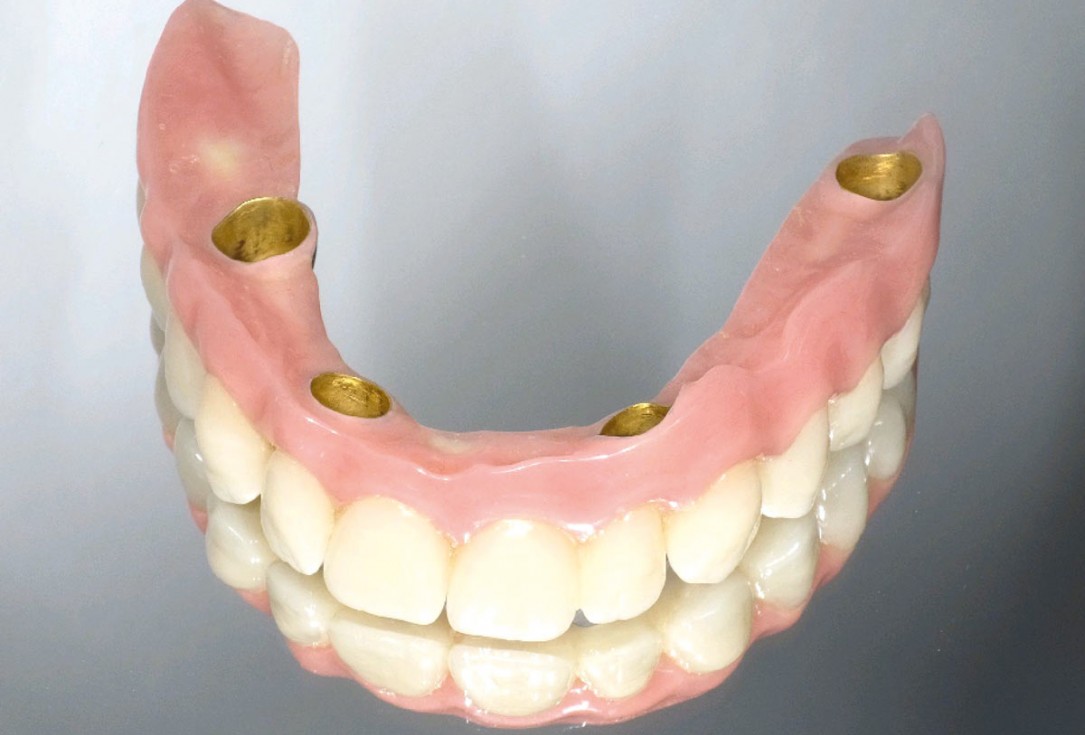

21/23 - Telescopic prosthesis

Full arch reconstruction of the maxilla with maxgraft® bonebuilder - Dr. M. Erbshäuser